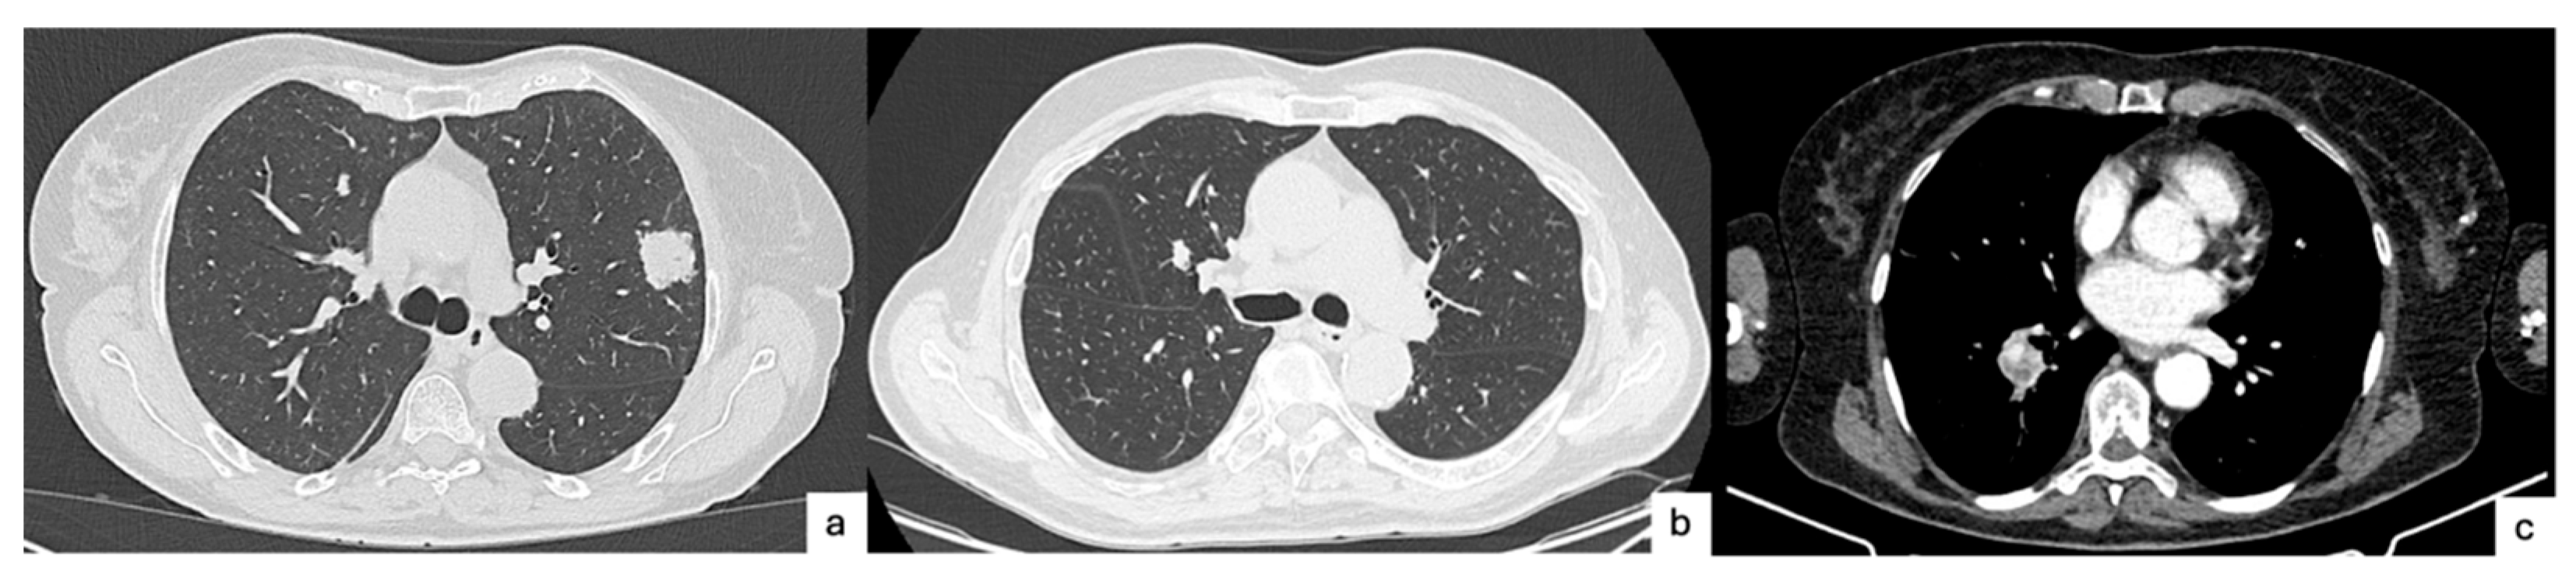

- Yoon, H.J.; Kang, J.; Lee, H.Y.; Lee, M.A.; Hwang, N.Y.; Kim, H.K.; Kim, J. Recurrence dynamics after curative surgery in patients with invasive mucinous adenocarcinoma of the lung. Insights Imaging 2022, 13, 64. [Google Scholar] [CrossRef]

- Lee, M.A.; Kang, J.; Lee, H.Y.; Kim, W.; Shon, I.; Hwang, N.Y.; Kim, H.K.; Choi, Y.S.; Kim, J.; Zo, J.I.; et al. Spread through air spaces (STAS) in invasive mucinous adenocarcinoma of the lung: Incidence, prognostic impact, and prediction based on clinicoradiologic factors. Thorac. Cancer 2020, 11, 3145–3154. [Google Scholar] [CrossRef] [PubMed]

- Toyokawa, G.; Yamada, Y.; Tagawa, T.; Kamitani, T.; Yamasaki, Y.; Shimokawa, M.; Oda, Y.; Maehara, Y. Computed tomography features of resected lung adenocarcinomas with spread through air spaces. J. Thorac. Cardiovasc. Surg. 2018, 156, 1670–1676.e4. [Google Scholar] [CrossRef]

- Kim, S.K.; Chung, M.J.; Kim, T.S.; Lee, K.S.; Zo, J.I.; Shim, Y.M. Lung Adenocarcinoma: CT Features Associated with Spread through Air Spaces. Radiology 2018, 289, 831–840. [Google Scholar] [CrossRef] [PubMed]